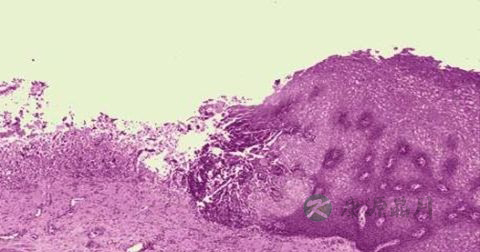

1、本病是由DNA病毒的单纯疱疹病毒所致。人类单纯疱疹病毒分为两型,即单纯疱疹病毒Ⅰ型(HSV-Ⅰ)和单纯疱疹病毒Ⅱ型(HSV-Ⅱ)。Ⅰ型主要引起生殖器以外的皮肤、粘膜(口腔粘膜)和器官(脑)的感染。Ⅱ型主要引起生殖器部位皮肤粘膜感染。此两型可用荧光免疫检查及细胞培养法相鉴别。

2、人是单纯疱疹病毒的唯一自然宿主。病毒经呼吸道、口腔、生殖器粘膜以及破损皮肤进入体内,潜居于人体正常粘膜、血液、唾液及感觉神经节细胞内。原发性感染多为隐性,大多无临床症状或呈亚临床表现,仅有少数可出现临床症状。原发感染发生后,病毒可长期潜伏于体内。正常人群中约有50%以上为本病毒的携带者。HSV在人体内不产生永久免疫力,每当机体抵抗力下降时,如发热、胃肠功能紊乱、月经、妊娠、病灶感染和情绪改变时,体内潜伏的HSV被激活而发病。

3、研究证明,复发性单纯疱疹患者可有细胞免疫缺陷。一般认为HSV-Ⅱ型与宫颈癌发生有关。